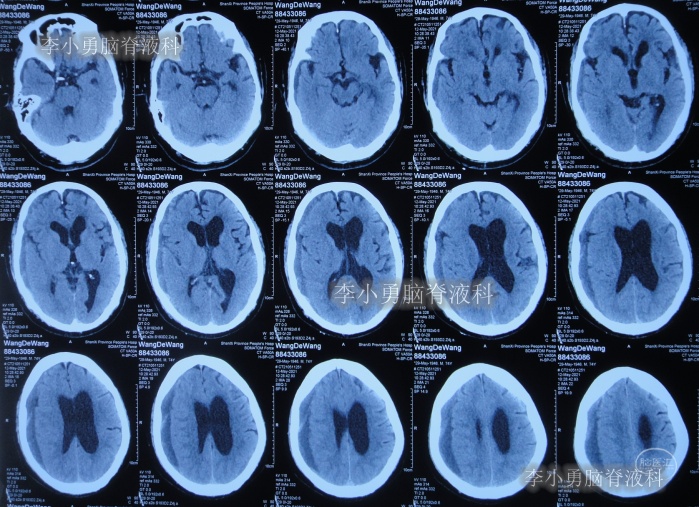

2020年10月29日(发病已8年),因症状一直没有得到改善且呈进行性加重趋势,查头部核磁示脑积水(图-1)。

图-1:2020年10月29日头部核磁

发现脑积水后8天即2020年11月6日,就诊于第2家的上海的某三甲医院,入院后再次检查(图-2)后诊断为正常压力脑积水。

图-2:2020年11月11日头部核磁